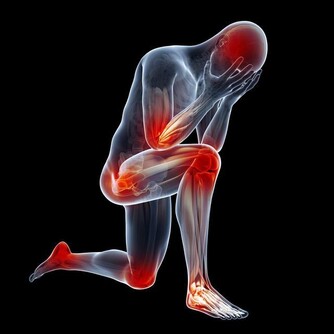

6、肩頸臂痛而且會轉移今天脖子疼,第二天改成了下巴疼,或是今天疼,第二天又不疼了。這是因為心臟缺血,

心臟缺血時時將疼痛信號通過神經傳遞反映在水平相同的脊髓段區域,

附近的器官如肩膀、脖子、下巴、手臂就在這個範圍內,會感覺到痛感。